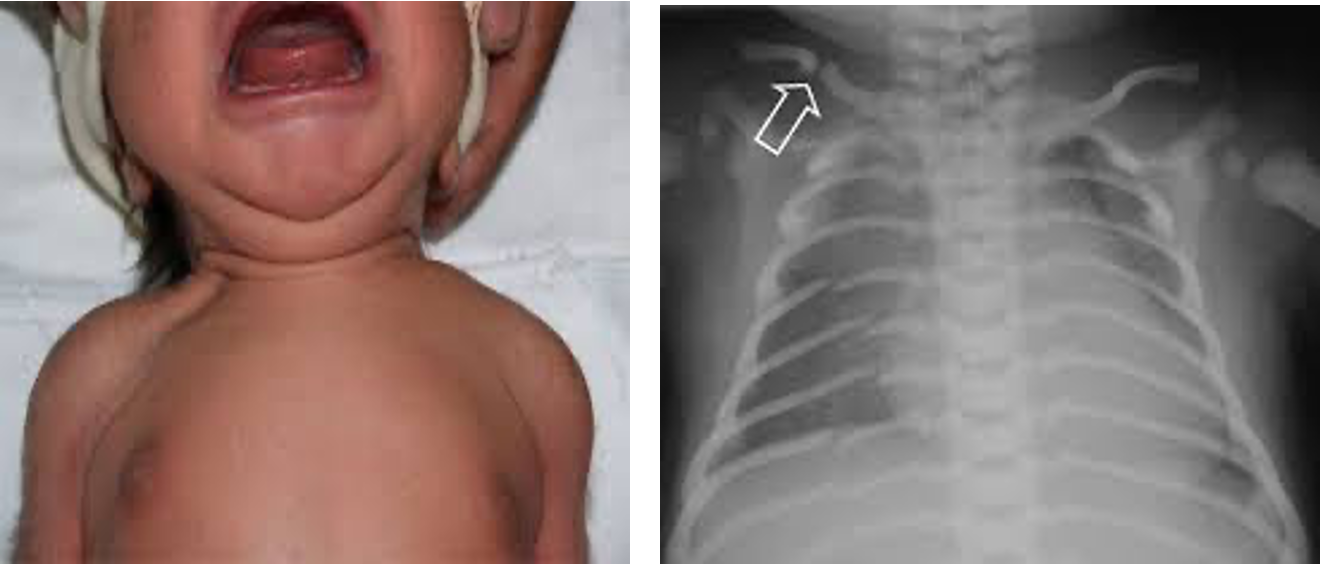

Clavicle:

- The most common fracture.

- A snap may be heard at delivery or the infant may have reduced arm movement on the affected side, or a lump from callus formation later, and unilateral absence of Moro reflex.

- Usually from shoulder dystocia.

- Management: nothing as it heals spontaneously.

Skull:

- Linear fractures → observe only.

- Depressed fracture → should be evaluated even if there are no neurological deficits.

Long Bones: Humerus/Femur

- Usually, midshaft, occurring at breech deliveries.

- Fracture of the humerus at shoulder dystocia.

- There is a deformity, reduced movement of the limb, and pain on movement.

- They heal rapidly with immobilization.